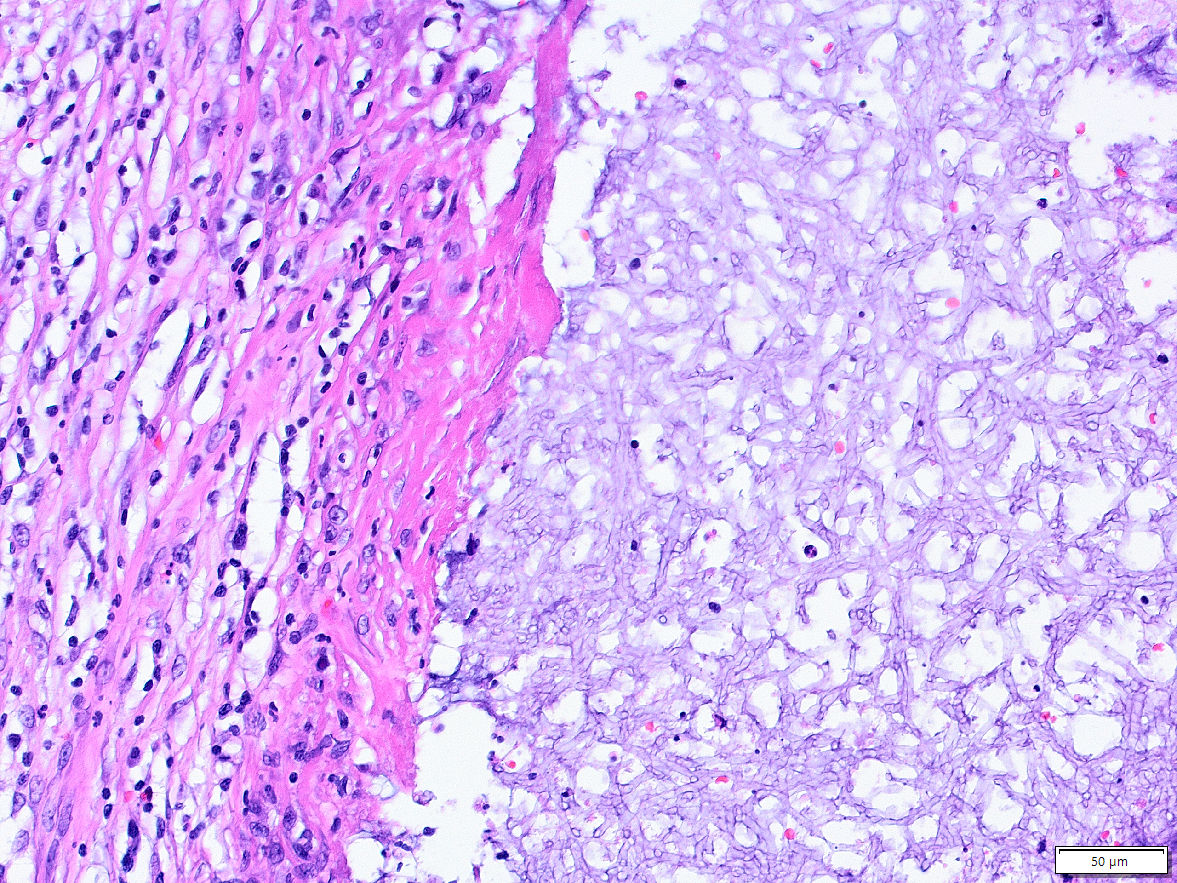

2. Man erkennt den Atemweg hier noch an der typischen Epithelauskleidung (mit Flimmerhärchen). Unter dem Epithel (also hier oben) ist ein "rundzelliges" Entzündungsinfiltrat. Also vorwiegend Lymphozyten und Plasmazellen - träger der chronischen Entzündung. Im Luftraum selber sind Pilzhypen.

3. Der Hohlraum ist aber nicht überall durch "Atemwegsepithel" ausgekleidet. Hier sieht es anders aus. Das ist Plattenepithel. Eine Metaplasie -> Das Epithel hat die Differenzierung geändert um dem dauernden Reiz besser entgegenstehen zu können.